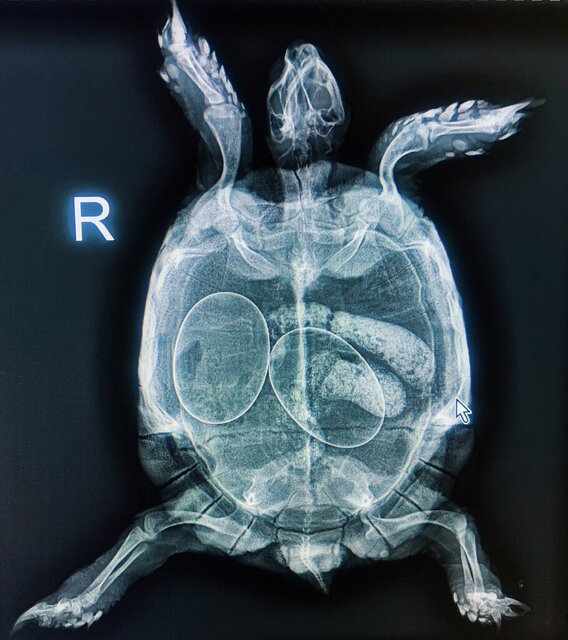

сейчас использую кукурузный наполнитель. Черепаха по чуть-чуть ходит в туалет. Но меня смущают светящиеся какашки на рентгене, это может быть песок? Еще пару недель назад содержалась в песке. Запоров никогда не было, но когда заметила в кале песок в больших количествах, поменяла наполнитель. Теперь переживаю, что «колбаса» на рентгене - каловые массы с песком.

Постоянно тужится, возможно к кладке готовится. Боюсь, что помимо яиц еще и непроходимость. Рентген сделан после купания (обычно при купании все выходит).